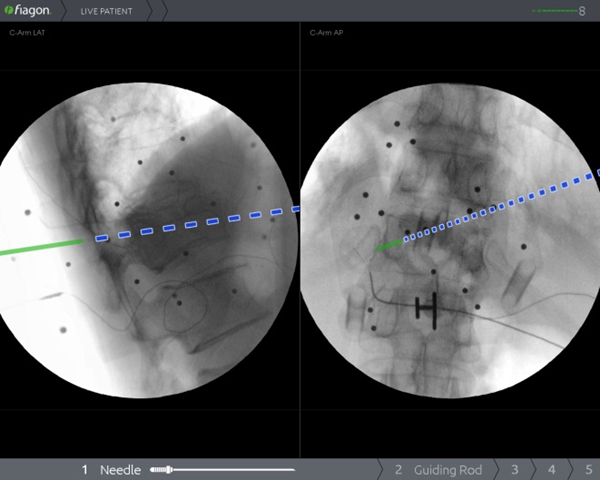

过去,受限于技术和设备,在脊柱上做手术,犹如在“暗箱”内操作,需要反复进行X线透视来判断术中状况,手术时间长,神经、血管损伤风险大。脊柱手术通常需要置入多枚螺钉,在没有先进设备辅助的情况下,医生只能凭经验操作,增加了相应的手术风险。脊柱手术的精准性和安全性一直是医生和患者最为关注的问题。而Joimax电磁导航系统作为目前世界最知名的导航系统,无传统光学导航系统“红外线遮挡”问题,并且不占用手术空间、可弯曲器械能实现尖端导航、定位器小巧,能实现多节段同步导航。骨二科(脊柱外科)李浩鹏主任表示,将导航系统应用于脊柱手术中,可以为医生呈现实时、直观的三维影像导航信息,帮助医生准确规划和及时更新手术方案,提高置钉的准确性,降低误伤神经、血管的风险,有效减少手术并发症,缩短住院时间,帮助患者及早恢复日常生活。

2020年1月9日,骨二科(脊柱外科)王栋教授团队成功将电磁导航技术引入到脊柱手术中,开展了医院首例电磁导航腰椎后方椎间融合术(PLIF)和首例电磁导航经皮穿刺椎体成形术(PVP)。手术当日,通过简单的安装信号发射器、定位仪并进行2D影像认证后,王栋教授团队在导航的辅助下,轻松完成原先脊柱手术中风险巨大的椎体植钉过程,随后的椎管减压及水泥注入等步骤一气呵成,有效缩短了手术时间、术中投射次数,大大降低了手术风险。